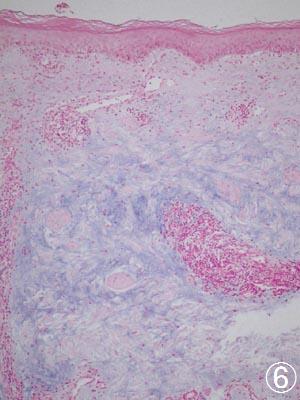

エリテマトーデス ムチン沈着

D皮膚のエリテマトーデス。自分の免疫力が自分の組織を攻撃してしまう「膠原病」の1種であり、石垣のように見える皮膚の細胞層の基底部が抜けたように変性している。E同じ病変の深層では、特殊な染色で青く染まる粘液が、線維間に溜まっていおり、通常の皮膚炎とは全く異なる所見がみられる。